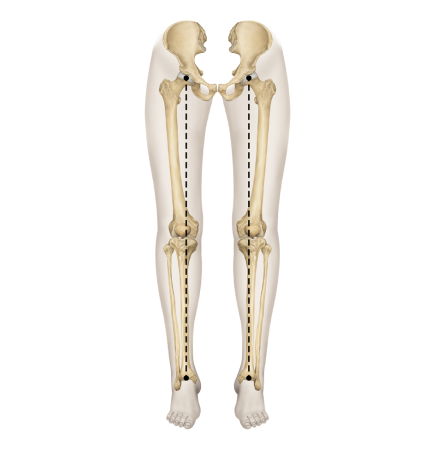

▲ O자 다리

▲ X자 다리

▲ 정상 다리

다리의 각도와 회전에 따라

경사형 휜다리

발의 변형이나 요족 및 걸음걸이 이상으로 무릎에 비정상적인 힘이 작용하며 생김

회전형 휜다리

고관절과 무릎이 내회전되어 발,발목 변형 동반되는 경우가 많고, 척추와 골반이 함께 틀어짐

복합형 휜다리

전면은 회정형 원다리처럼 보이나 경사형과 회전형 원다리 특징을 모두 가진 형태

특발형 휜다리

특발성측만증을 동반하거나 사고로 인한 경우 또는 다리 길이 차이 등 구조적 문제를 동반

휜다리는 단순히 무릎 사이 간격이 벌어진 것이 아닙니다.

무릎 위의 대퇴골과 아래의 정강이뼈가 회전하면서 무릎까지 뒤로 빠지기 때문에 다리사이 간격이 넓어지는 겁니다.

발(아치)-발목-무릎관절-고관절-골반의 서로 다른 회전을 바로 잡는 기술입니다.